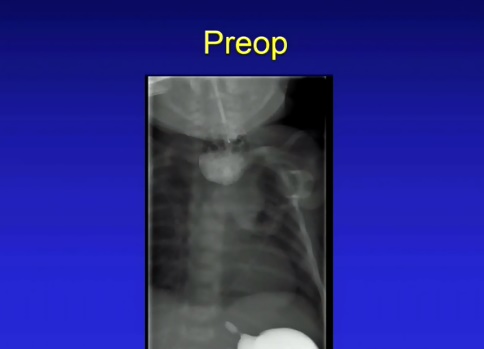

Operasyonun gerçekleştirildiği Henryk Deneen isimli bebeğin 33 haftalık doğduğu aktarılarak, bebekte özofagus atrezisi adı verilen ve özofagusun bir kısmının eksik olduğu doğum kusuru bulunduğu kaydedildi.

Özofagus atrezisi ile doğan çocukların yemek yiyemediği veya yutamadıkları hatırlatılarak, bu durumdaki bebeklere 3 aylık olduktan sonra operasyon yapılabildiği ve cerrahi operasyonla yemek borusunun üst ve alt kısımları arasındaki boşluğun bağlandığı bildirildi.

Bebek Deneen'in yemek borusunun eksik kısmının çok büyük olduğunu gören operasyon ekibinin, daha önce hiç denenmemiş bir hibrit prosedür geliştirdikleri belirtildi. Buna göre doktorlar, cerrahi olarak Deneen'in karnına girecek, midesinin bir kısmını göğsüne doğru çekecek ve ardından organların uçlarını birbirine doğru germek için iki mıknatıs bağlayacaktı. Ekip ayrıca bebeğin yemek yemesine yardımcı olmak için el yapımı bir de stent geliştirdi.

Ameliyatın ardından bir hafta boyunca röntgenlerle kontrol edilen mıknatısların çalışması, Deneen'in ailesini sevince boğdu.